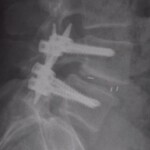

Ἡ νόσος εἶναι ἐπίκτητος, στὴν Εὐρώπη δὲ ἀφορᾶ δὲ τὸ 5% τῶν ἐνηλίκων καὶ 2% τῶν ἐφήβων καὶ παιδιῶν. Οἱ στατικὲς συνέπειες τῆς σπονδυλύσεως-σπονδυλολισθήσεως εἶναι: Ἐξάλειψη τῆς φυσιολογικῆς ὀσφυϊκῆς λορδώσεως ἢ καὶ μετατροπή της σὲ ὀσφυϊκὴ κύφωση (εἰκ. 8), ἐξάλειψη τῆς φυσιολογικῆς θωρακικῆς κυφώσεως, ἐλαττωμένη εὐλυγισία κινήσεων τῆς λεκάνης, μετατόπιση τοῦ κέντρου βάρους τοῦ σώματος πρὸς τὰ πρόσω (κοιλιακά), ἐλάττωση τοῦ ὕψους τοῦ κορμοῦ. Ἐντυπωσικὸ ὅμως εἶναι ὅ,τι σὲ ὄχι εὐκαταφρόνητο ἀριθμὸ παιδιῶν δὲν ὑφίστανται ἀρχικῶς συμπτώματα, παρὰ τὰ τυπικὰ ἀκτινολογικὰ εὑρήματα. Μὲ διαρκῆ ὅμως παρουσία τῆς νόσου, ἀρχίζουν σταδιακὰ νὰ ἀναφύονται καὶ τὰ ἀναμενόμενα συμπτώματα. Τὸ κυρίαρχο σύμπτωμα εἶναι πόνος κατὰ τὴν διάρκεια κάποιων κινήσεων, πόνος ποὺ ἔχει ζωστηροειδῆ περὶ τὴν ὀσφὺ ἐπέκταση καὶ μὲ φορὰ ἀπὸ πίσω πρὸς τὰ ἐμπρός, εἰδικὰ τὸ πρωῒ, ὅταν οἱ μῦες τῆς ράχεως εἶναι χαλαροί. Ὑπάρχει ἐπίσης ἕνα αἴσθημα ἀστάθειας στὴν Σ.Σ.. Σὲ σοβαρὲς περιπτώσεις παρατηρεῖται ἀπώλεια ἀντανακλαστικῶν, ὑπαισθησία κάτω ἄκρων καὶ διαταραχὲς κινητικότητος. Τότε ἡ χειρουργικὴ θεραπεία (εἰκ.9) εἶναι μονόδρομος! Σὲ γενικὲς γραμμὲς τὰ συμπτώματα προσομοιάζουν μὲ ἐκεῖνα τῆς κήλης δίσκου (δισκοπάθεια).

Ἡ διεθνὴς ταξινόμηση τῶν σταδίων τῆς σπονδυλολισθήσεως ἀκολουθεῖ τὸν ὑποδειχθέντα ὑπὸ τοῦ Meyerding κανόνα, σύμφωνα μὲ τὸν ὁποῖο τὸ μῆκος τῆς ὀλισθήσεως ἑνὸς σπονδύλου εἶναι συνάρτηση τοῦ μήκους τῆς βάσεως τοῦ ὑποκειμένου σπονδυλικοῦ σώματος. Ἡ διάγνωση ἢ ἡ ὑποψία μιᾶς σπονδυλολύσεως καὶ κατὰ τὶς περιστάσεις τῆς σπονδυλολισθήσεως τίθεται μὲ μία πλαγία ἀκτινογραφία ΟΜΣΣ καὶ μὲ ἐπικέντρωση στὸ ὕψος Ο4-Ο5-Ῑ1. Ὀριστικὴ ἐπιβεβαίωση δίδεται διὰ τῆς διενεργείας λοξῆς (45ο) ἀκτινογραφίας, ὅπου ἡ ἀπεικονιζόμενη σπονδυλόλυση περιγράφεται συχνὰ μὲ τὸν ἀποδοθέντα ὑπὸ τῶν παλιῶν ἀκτινολόγων ὑπέροχο ὅσον καὶ γλαφυρὸ ἀκτινολογικὸ ὅρο: «ἡ φιγούρα τοῦ σκύλου μὲ τὸ κολλάρο» Τὸ κολλάρο τοῦ σκύλου εἶναι ἡ διαυγαστικὴ γραμμὴ τοῦ ρωγμώδους κατάγματος τοῦ σπονδυλικοῦ τόξου!! (Οἱ εἰκ. 10,11,12 καὶ 13) ἀκριβῶς παρουσιάζουν τὴν 4ετῆ πορεία ἑνὸς κοριτσιοῦ , ποὺ σὲ ἠλικία 10 ἐτῶν, ὑπέστη σπονδυλόλυση καὶ σπονδυλολίσθηση τοῦ Ο5 ἐπὶ τοῦ Ι1 κατὰ τὴν διάρκεια ἀσκήσεως μοντέρνου χοροῦ. Χαρακτηριστικὴ εἶναι ἡ ὕπαρξη τοῦ ἀκτινολογικοῦ κριτηρίου «τῆς φιγούρας τοῦ σκύλου μὲ τὸ κολλάρο»!!) Ἐὰν τὰ εὑρήματα στὶς ἀκτινογραφίες δὲν εἶναι σαφῆ, ἐπιβάλλεται περαιτέρω ἔλεγχος μὲ μαγνητικὴ τομογραφία.